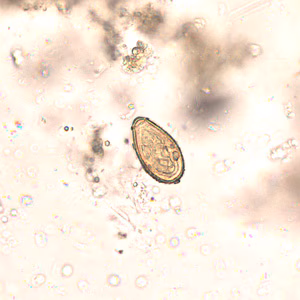

Eggs of Opisthorchis spp. in wet mounts.

Diagnosis is based on microscopic identification of eggs in stool specimens. However, the eggs of Opisthorchis are practically indistinguishable from those of Clonorchis. The adult fluke can also be recovered at surgery.